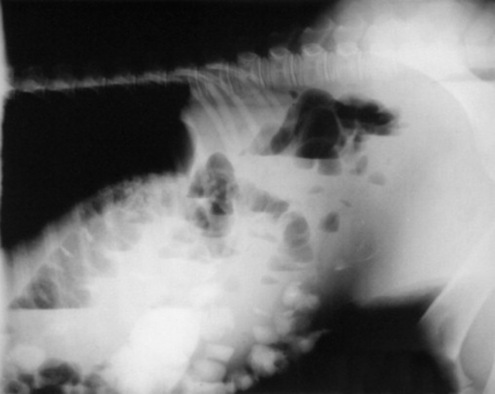

Serial thoracic radiographs are useful in monitoring the progress of a respiratory condition. Radiographic changes may either follow or precede changes in clinical condition, and major changes can occur surprisingly rapidly (Fig. 19-2). Clinical signs of pneumonia frequently resolve much earlier than chest radiographs and hemograms return to normal. Unfortunately, both ABG analysis and radiography are difficult to perform in field situations.

Fig. 19-2 A, Standing lateral chest radiograph of a 7-day-old thoroughbred filly with severe angular limb deformities that experienced an acute onset of severe respiratory distress and cyanosis after a walk outside the stall. Intubation and 100% oxygen administration raised the PaO2 to only 48 mm Hg. Severe pulmonary interstitial disease is present in the caudoventral lung fields, and the tentative diagnosis was bacterial pneumonia. No modifications were made in the treatment regimen (the same antibiotics being given for a wound were continued), and over the following 24 hours the filly clinically improved. B, Repeat radiographs taken 3 days after the first ones revealed marked resolution of the infiltrates. The diagnosis remains open, but pulmonary edema was suspected.